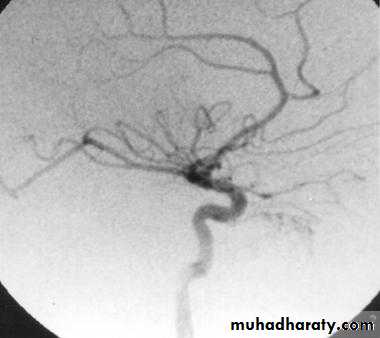

4- angiography: shows a vascular blush in the nasopharynx and is useful to determine the feeding vessel

Biopsy is contraindicated

Mainly surgical: At least 3 units of blood should be preparedThere are different techniques used preoperatively to reduce the tumor size and vascularity:

3- Embolization